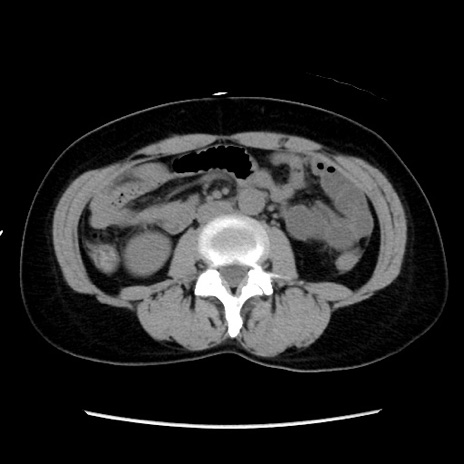

冠状断像

【症例】 50歳代女性

【主訴】 腹痛

【現病歴】前日生レバーを食べた。今朝に排便あり。 昼前に突然発症の腹痛を生じ、当院救急外来を受診した。

【既往歴】 子宮筋腫にてで子宮全摘後

【身体所見】 意識清明、腹部:平坦、軟、下腹部やや左を中心に圧痛・反跳痛あり、筋性防御あり

【データ】WBC 7800、CRP 0.07